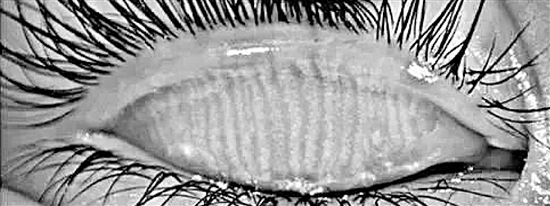

睑板腺功能障碍在我国较为常见,睑板腺功能障碍的患者常常出现泪液缺乏,导致泪膜不稳定,泪膜蒸发速率加快,泪液渗透压增加,造成干眼、睑板腺发炎等症状。因此,做好对于睑板腺功能障碍的预防工作十分重要。

4、眼睑冲洗:适用于眼睛干涩,且伴有眼睑有屑状物剥落(眼睑炎症状)的患者。眼睑炎是由于油脂分泌过多造成堵塞所致。眼部冲洗液有助于溶脂去屑,让眼睛更舒适。每晚用眼部冲洗液沿眼线擦洗按摩。如果连续几天症状无改善,应去看医生。